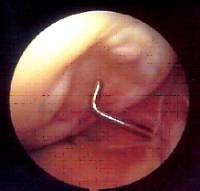

Menisc discoide

És una alteració congènita que afecta la morfologia i l’estructura del menisc, i és més freqüent externament.

Present entre l’1 i el 5% de la població, la simptomatologia clínica és molt variada segons l’extensió (complet / incomplet), així com del manteniment de les insercions capsulars.

El tractament és la meniscectomia parcial artroscòpica i la sutura en casos de desinserció.

En pacients asimptomàtics s’ha indicat el tractament quirúrgic preventiu pel fet que pot condicionar un hipocreixement del còndil femoral i perquè es tracta d’un menisc estructuralment anormal amb més susceptibilitat per patir lesions.